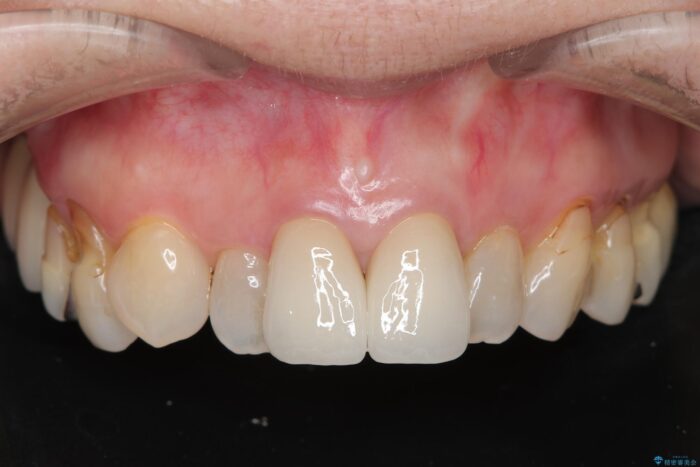

黒ずみもなくなり、自然な色味で大変ご満足いただけました。